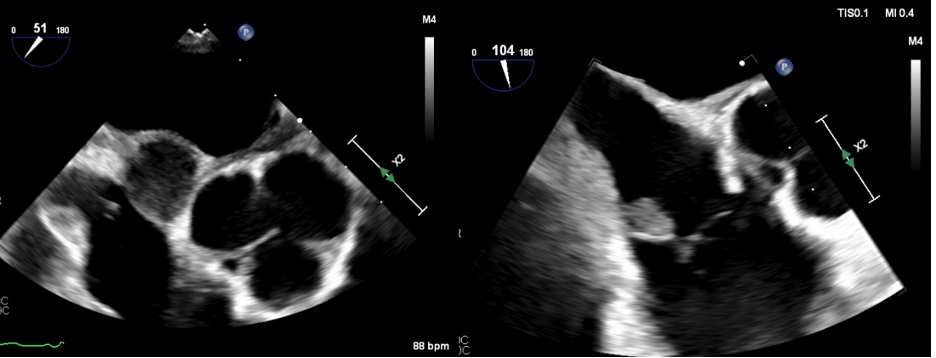

Short axis of the inter-atrial septal mass

Transesophageal echocardiogram showing homogenous mass within the inter-atrial septum (left). Transesophageal echocardiogram demonstrating tricuspid vegetation (right)..png)